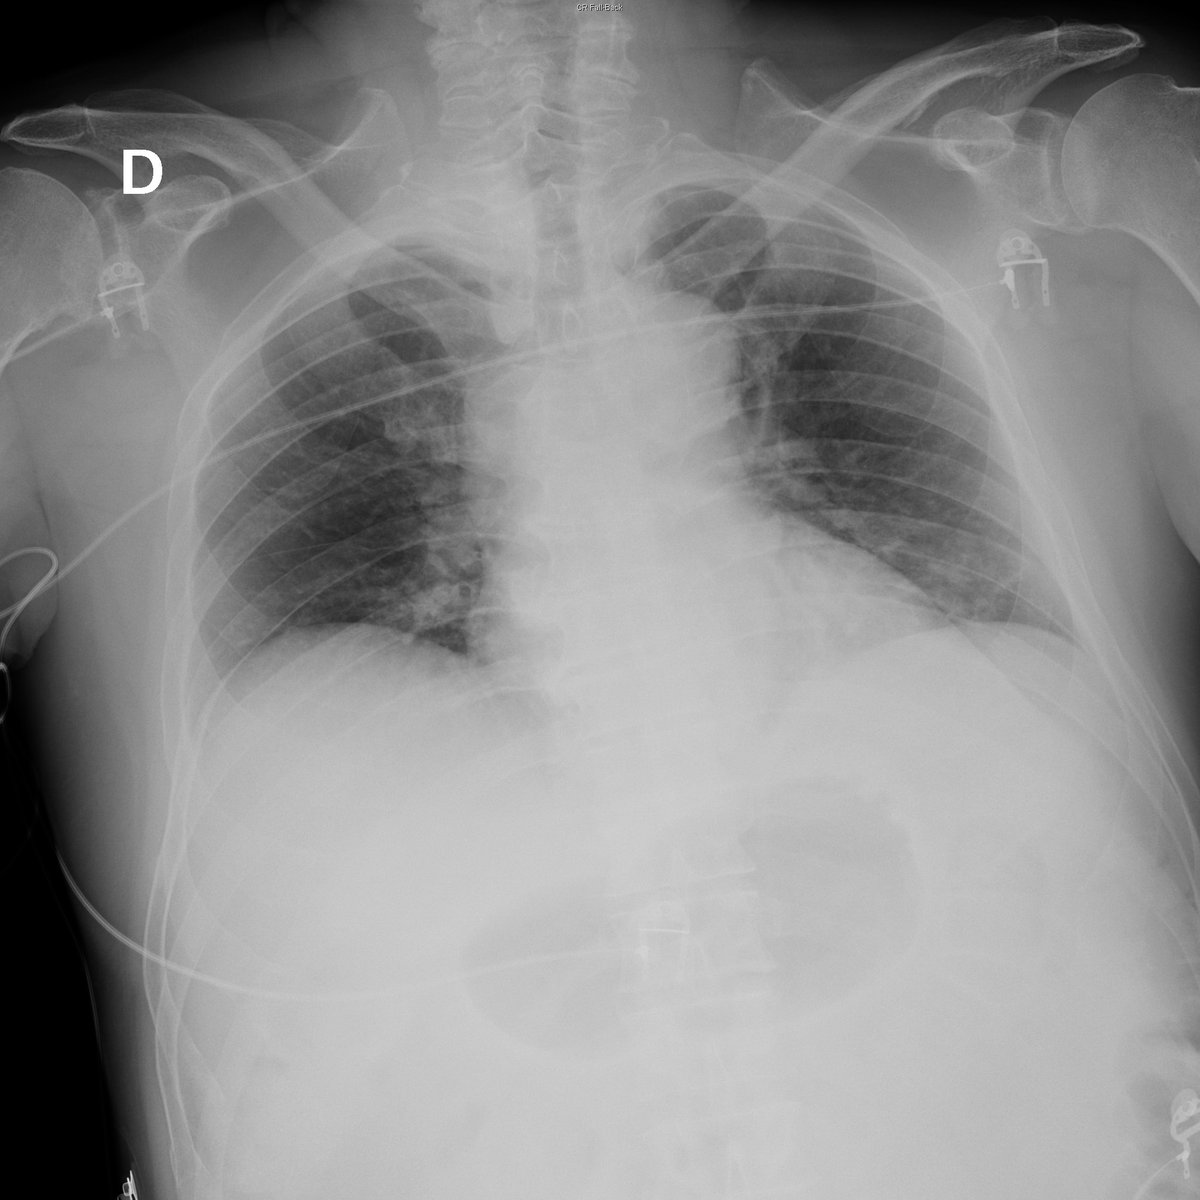

Case 1. 68yo female. Cough and fever.